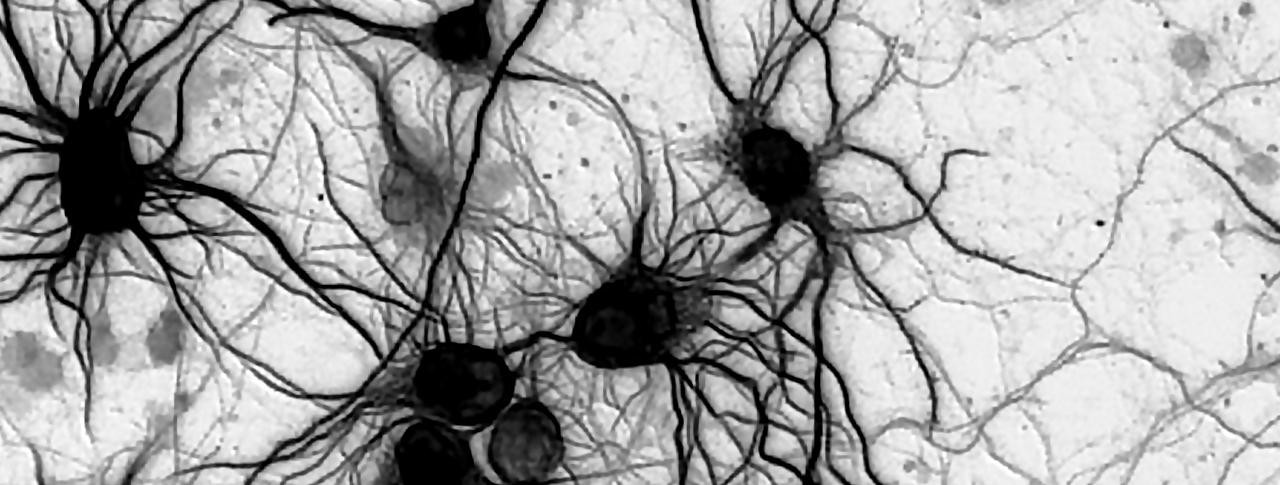

In parallel, Novartis scientists within the Developmental & Molecular Pathways and Neuroscience groups set out to determine exactly how the mutations affect brain cells. Carleton Goold, Sue Menon and their teams introduced them into rat neurons, which proceeded to grow very large. The researchers also tested mTOR pathway activity in the neurons and confirmed that it was elevated.

The final step was to rescue the swollen cells. When the team applied an mTOR inhibitor to the mutant neurons, the cells shrank to a healthy size, pointing toward a potential therapeutic strategy for patients.

Researchers introduced an mTOR mutation identified from focal cortical dysplasia patients into these rat neurons. The neurons are enlarged, similar to what is seen in brain tissue from the patients. Image by Jonathan Biag/Novartis